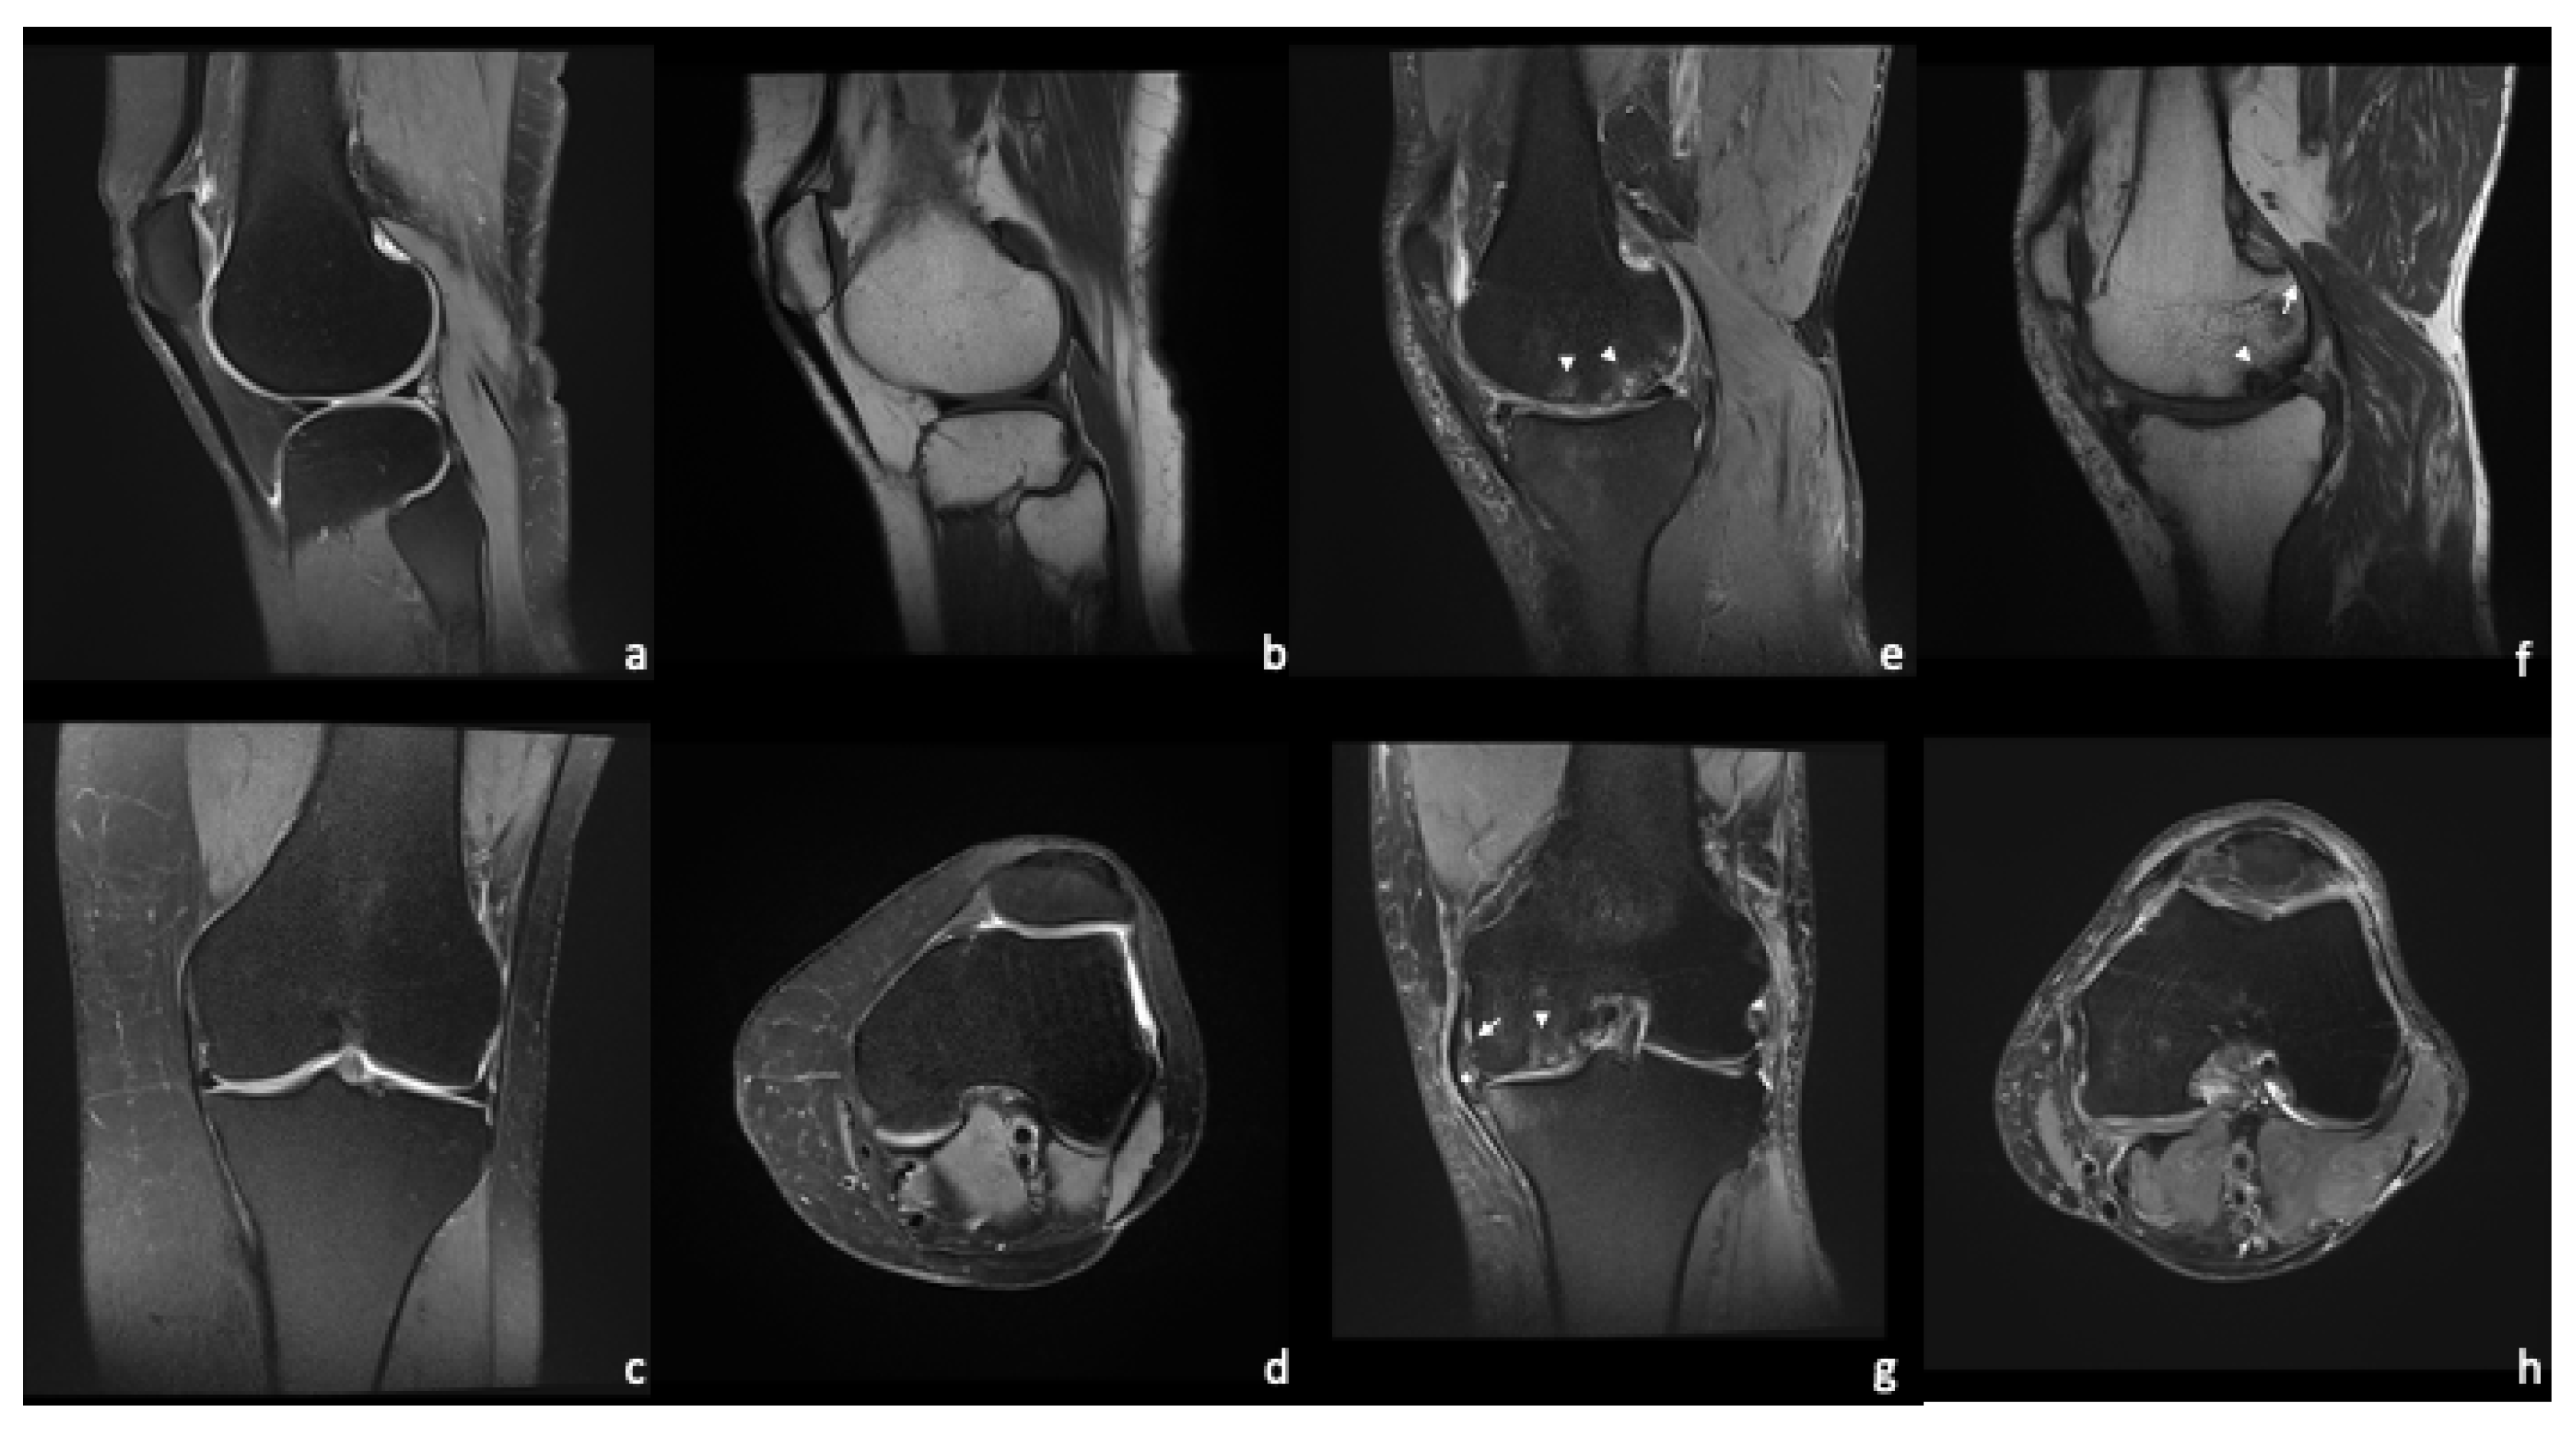

4. Magnetic Resonance Imaging—Common Findings

While radiography visualizes relatively late and mostly irreversible stages of OA, MRI has the potential to detect pre-osseous deformities. A common MRI finding in OA is articular cartilage damage. Bone marrow lesions (BML) in the subchondral bone and subarticular cysts reflect extensive remodeling of the subchondral bone [13,46]. BML appear as PDw-hyperintense lesions and can be found in early OA. A study by Muratovic et al. found that BML that also appear on T1w-images are associated with late OA [47]. Subarticular bone loss and marginal osteophytes may also be seen. In the surrounding tissues, damage to the cruciate and collateral ligaments as well as the menisci may be found. Periarticular cysts, synovitis, joint effusion, and loose intraarticular bodies are considered diagnostic [12,48]. Figure 3 shows a standard MRI protocol for the knee comparing a physiological joint to a severe OA of the medial compartment.

Figure 3. Standard protocol for knee evaluation. Healthy knee joint (ad) vs. severe OA of the medial compartment (eh) with BML (arrowheads), meniscal extrusion (star), and small osteophytes (arrows). The articular cartilage shows irregular thickness with some full thickness lesions (g).